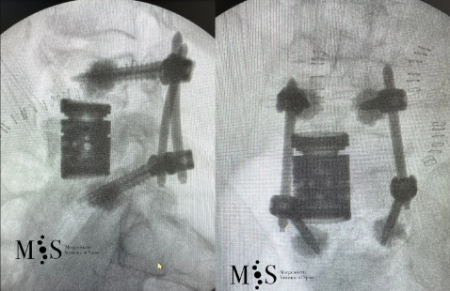

Clinical case example of a lumbar vertebral body resection (corpectomy) and reconstruction of a burst fracture at level L4.

Severe vertebral body fractures, i.e. conminute and burst fractures, may require a partial vertebral body resection (corpectomy) and reconstruction with an expandable vertebral body cage. Especially severe fracture cases are also those with a bone fragment moving into the spinal canal that compresses on neural structures, such as the spinal cord and causes spinal canal stenosis. Corpectomy allows to resect most of the fractured body, including the bone fragments pushing on the nerves and intruding into the spinal canal. The vertebral body reconstruction is usually rounded up with a posterior augmented instrumented fusion of the adjacent levels to the fracture. All of this allows a proper healing of the fracture and the patient to recover without pain.